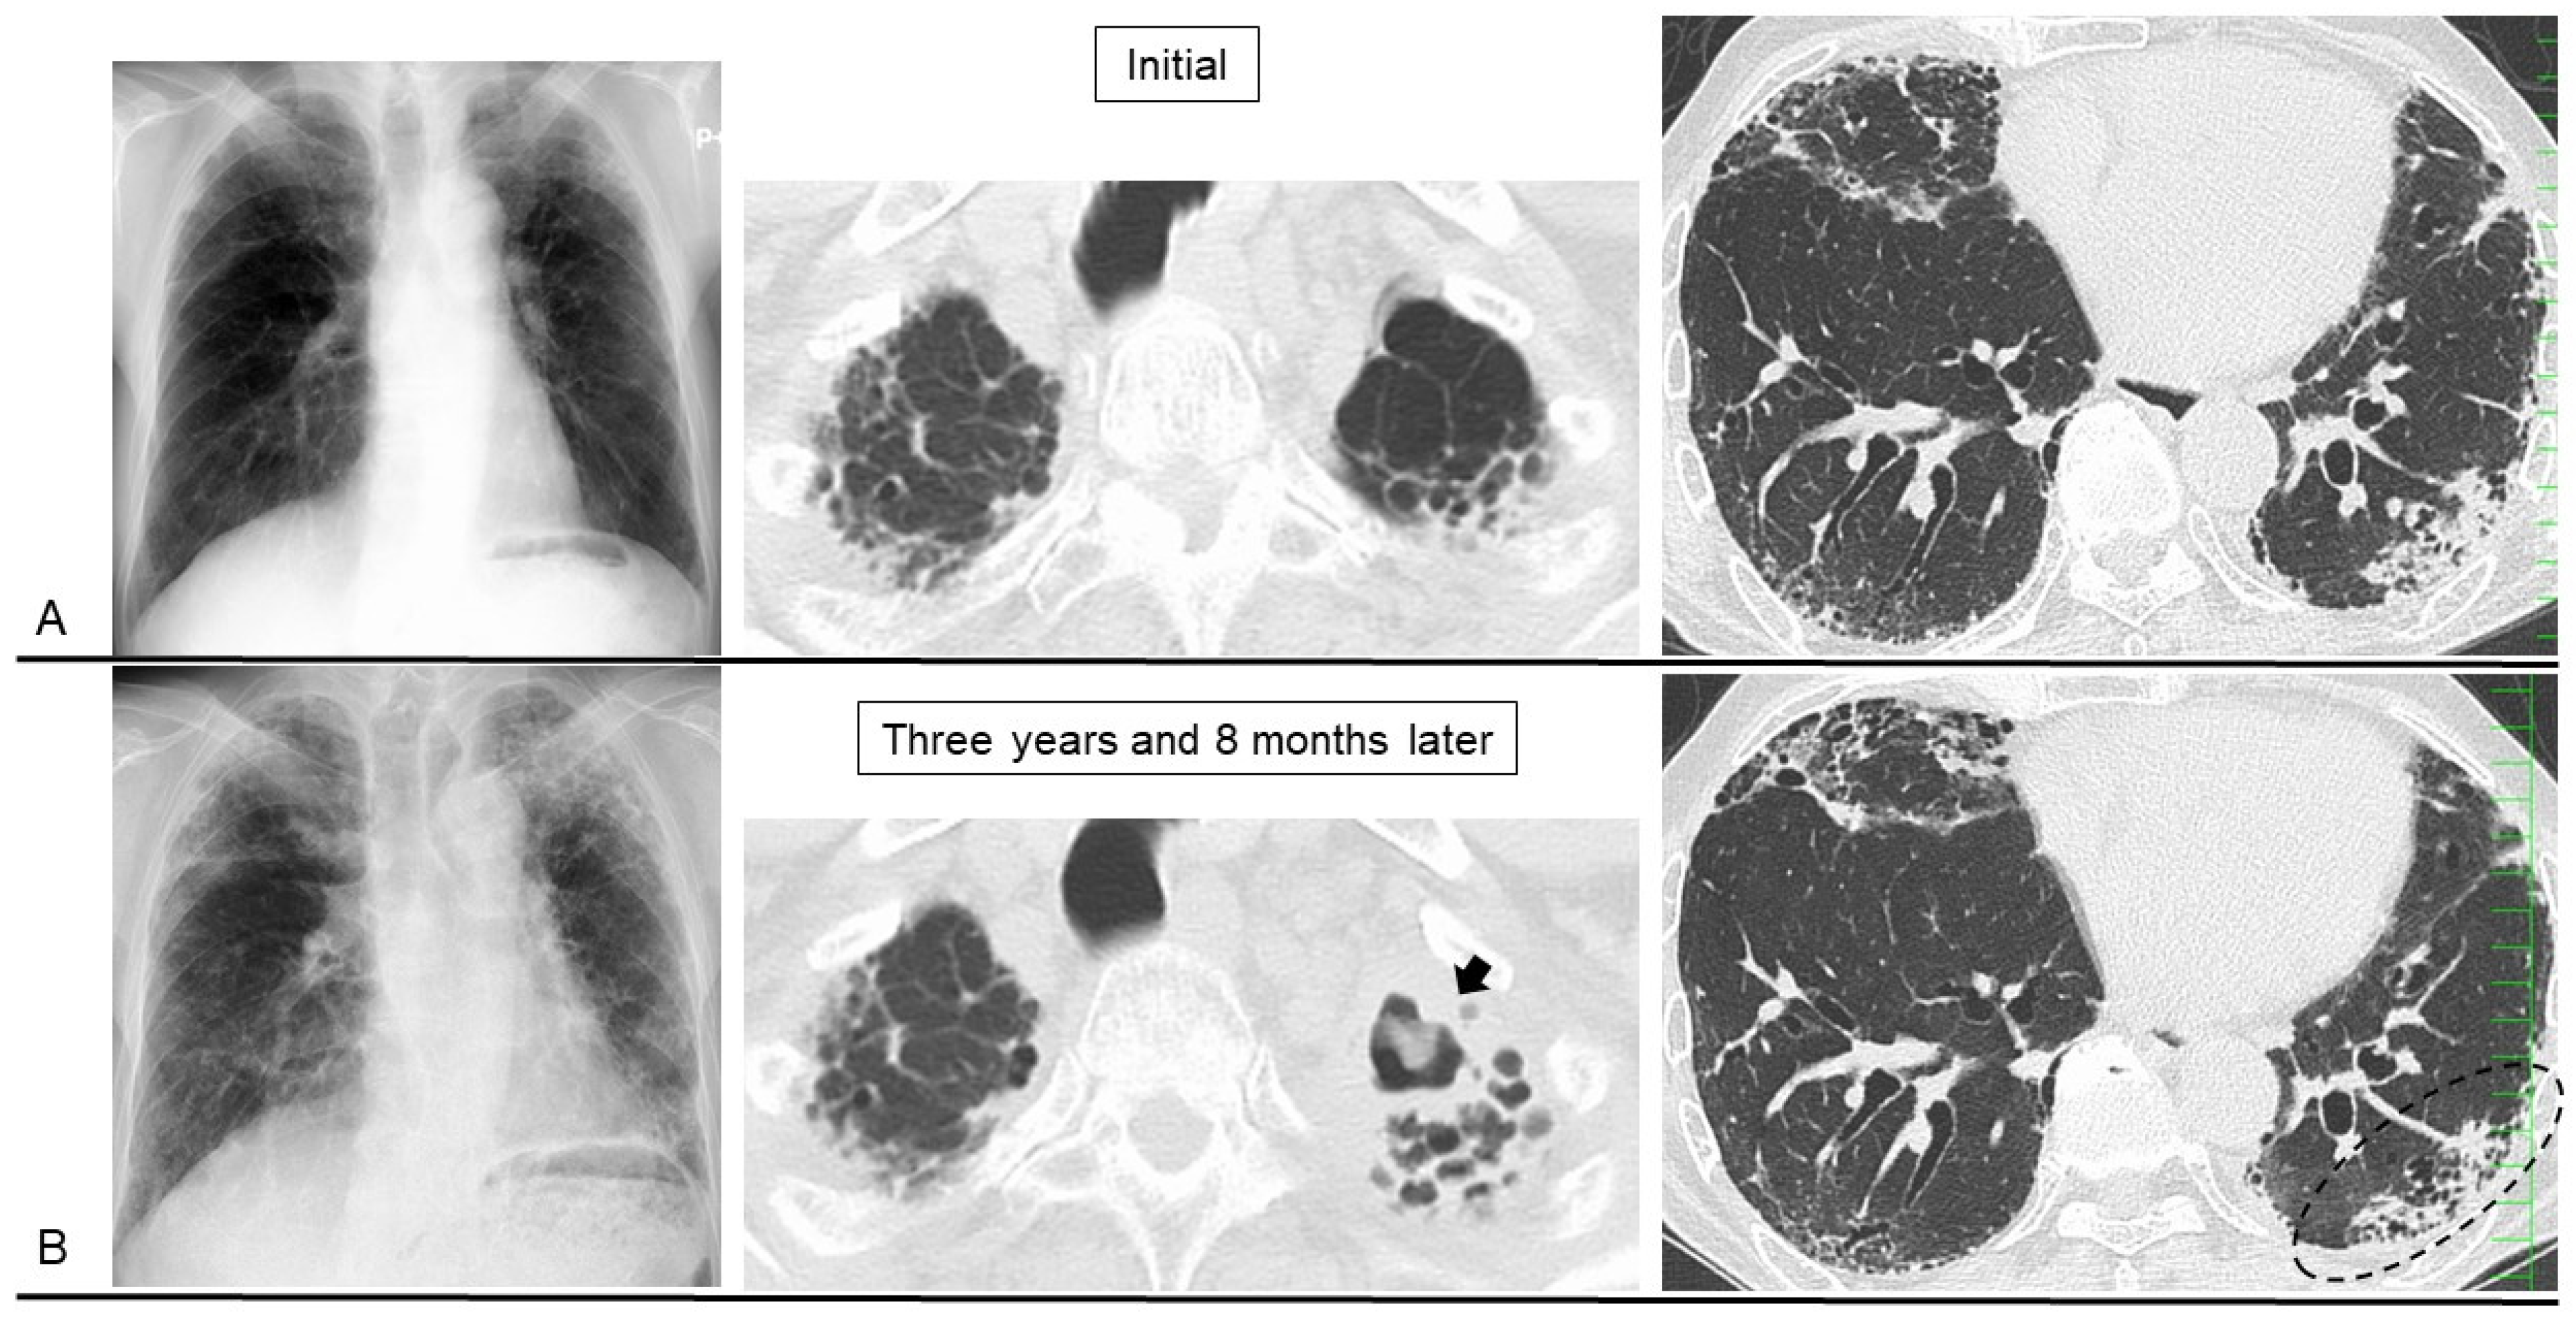

4. Secondary PPFE